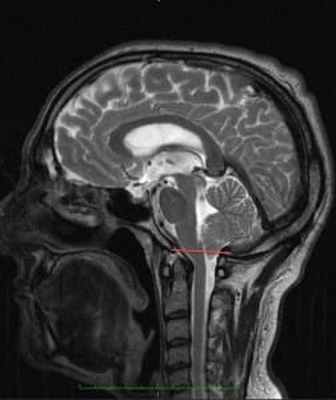

МРТ головного пациента с ААК I типа – смещение миндалин мозжечка в позвоночный канал

ниже уровня большого затылочного отверстия (более 6 мм)

МР-картина ААК II типа – четко визуализируется каудальное смещении нижних отделов червя мозжечка,

продолговатого мозга, а также гидроцефалия